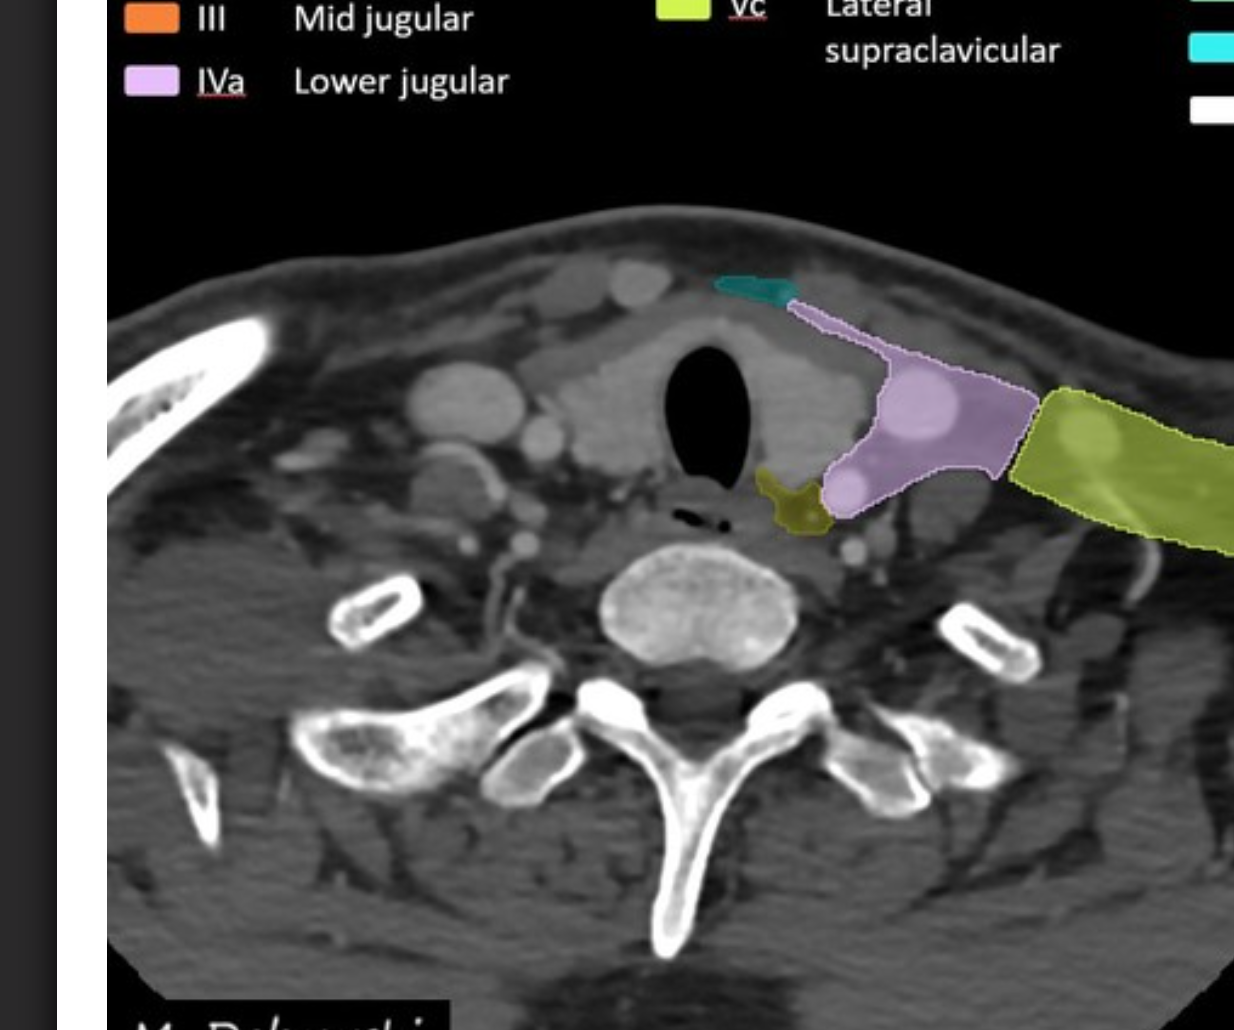

Level V lymph nodes

Boundaries

superiorly:

inferiorly:

anteriorly:

posterolaterally:

medially

There are two sublevels:

Level V: posterior triangle

superiorly: skull base at the apex of the convergence of sternocleidomastoid and trapezius muscles

inferiorly: level of the clavicle

anteromedially: posterior border of the sternocleidomastoid muscle

posterolaterally: anterior border of the trapezius muscle

level Va: superior half, superior to inferior border of the cricoid cartilage (posterior to levels II and III); includes spinal accessory nodes

level Vb: inferior half, inferior to inferior border of the cricoid cartilage (posterior to level IV); includes lateral supraclavicular nodes 1